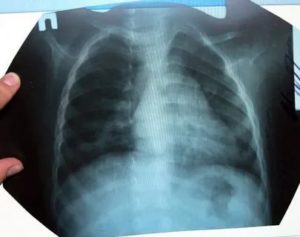

Рентген является современным способом диагностики многих заболеваний дыхательной системы. Без него часто не обойтись при постановки диагноза пневмонии у детей.

Диагностика пневмонии у детей с помощью рентгена вызывает ряд некоторых трудностей. Связано это с небольшим объемом легочной ткани и большим количеством структурных элементов на маленькую площадь, которая подлежит исследованию. Из-за этого появляется сложность в правильной оценке легочного рисунка, а также диагностирования состояния легочных корней и лимфоузлов.

Самым распространенным признаком пневмонии у детей, которые проявляются на снимках, являются очаговые тени в нижних сегментах легких диаметром 1-2 мм.

Пневмония на рентгенограмме у пациентов детского возраста не имеет выраженных отличий от взрослых, патология также характеризуется очагами просветления и затемнения. У детей в воспалительный процесс вовлекаются нижние отделы лёгких.

Рентгенография показывает следующее:

- очаговые затемнения диаметром 1-2 мм;

- увеличение внутригрудных лимфоузлов;

- деформация и усиление лёгочно-сосудистого рисунка;

- повышенная плотность затемнения (запущенная патология);

- в области патологического очага изменяется структура и размер лёгочного корня.

Хоть общая картина детского рентгена не различается от взрослого, некоторая разница имеется. Первое — повышенная реактивность функций иммунной системы.

Поэтому даже незначительный инфильтрат способен спровоцировать воспалительную реакцию на обеих долях лёгкого.

При постановке диагноза ребёнку можно ошибиться, что связано с небольшим объёмом лёгочной ткани и повышенным присутствием лёгочного рисунка.

У детей это заболевание на снимках выглядит немного иначе, чем у взрослых. Это объясняется тем, что организм ребенка реагирует на любое воспаление намного острее. Даже самый маленький инфильтрат может стать причиной крупозной формы болезни.

На рентгеновском снимке воспаление легкого у ребенка выглядит следующим образом:

- Очаги затенения локализуются в нижних отделах легких.

- Размеры инфильтратов очень маленькие. Чем выше их плотность, тем тяжелее болезнь.

- В средостении отмечается увеличение лимфатических узлов. Это отчетливо видно на рентгене.

- Участки поражения могут смазывать структуру корня легкого и полностью скрывать рисунок легочной ткани.

Из-за того, что у детей легочная ткань нередко вздувается без всякого воспаления, диагностировать пневмонию на начальных стадиях развития с помощью рентгеновских снимков бывает достаточно сложно. Кроме того, правильную диагностику при пневмонии у детей мешает поставить малый объем легочной ткани.